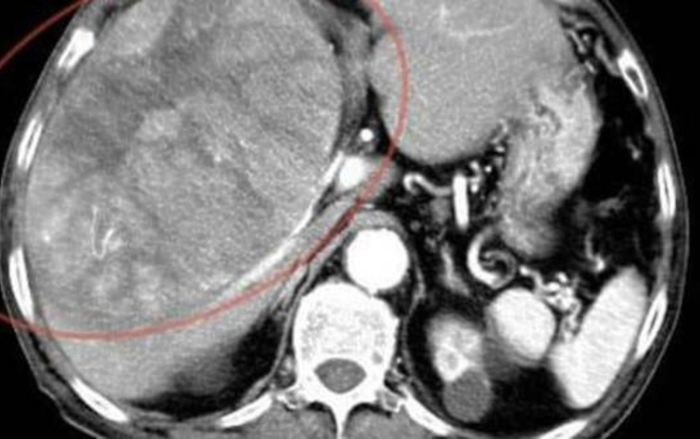

Gia đình cho rằng việc ông sụt 3-4 kg trong vài tháng là tác dụng phụ của thuốc. Nhưng thực tế, thể lực của ông suy giảm rõ rệt. Hai tháng sau, ông xuất hiện triệu chứng đau bụng vùng trên bên phải và trào ngược axit. Khi đến phòng khám, bác sĩ phát hiện một khối u lớn 15 cm trong gan. Kết quả chụp CT xác nhận ông mắc ung thư gan giai đoạn cuối và không thể can thiệp phẫu thuật. Chỉ ít lâu sau khi bắt đầu điều trị, ông qua đời. Gia đình bàng hoàng: "Ông nội sống rất điều độ, ăn uống lành mạnh, vì sao vẫn mắc ung thư gan?".

Ăn uống quá lành mạnh, cụ ông ngoài 80 tuổi mắc ung thư gan giai đoạn cuối Ảnh 2